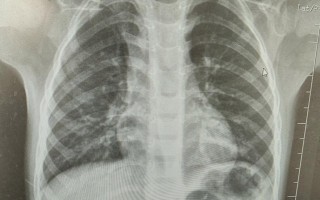

新生儿健康护理 新生儿拍肺部CT影响有多大? 这是一个非常严肃且重要的问题,所有家长在面临这个抉择时都会感到焦虑和担忧,我们来详细、客观地分析一下新生儿做肺部CT的影响,帮助您做出更明智的决定,新生儿肺部CT检查是一把“双刃剑”,它带来的明确诊断... 99ANYc3cd6 2025-11-30 0 #新生儿肺部CT辐射影响 #婴儿拍肺部CT的危害 #新生儿CT检查风险大吗